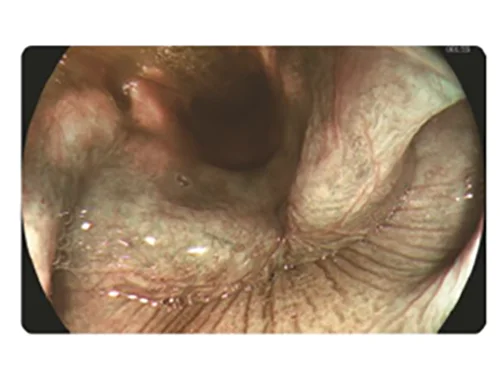

DSI

PSI: Спектральная визуализация цветовой палитры полихроматическая визуализация

Выравнивает пропорции узкополосного фиолетового и красного цвета на основе белого цвета и использование алгоритмов сложения для повышения цветового контраста.

Белый свет

PSI